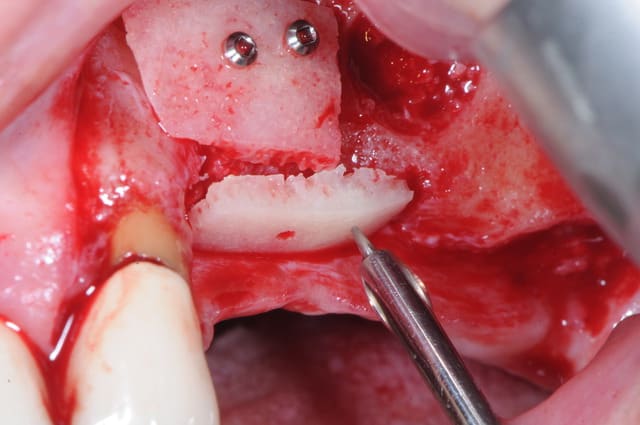

et le biobank c'est quand même génial ce truc, on gagne un temps fou.

ici, avec le sinus lift réalisé avec le DASK (merci Michael B.) et avec la greffe d'apposition j' mis 1h45mm. un vrai bonheur !

j'ai rien ajouté , pas de membrane, je l'ai joué à la Fouad Khoury (en moins bon évidemment.)

Uniquement l'os Biobank en poudre, il a un aspect assez mou et agréable à manipuler.

En faisant une scarification haute du périoste

Pas d'épaisseur partielle, mais totale . Ainsi tu ne risques pas grand chose